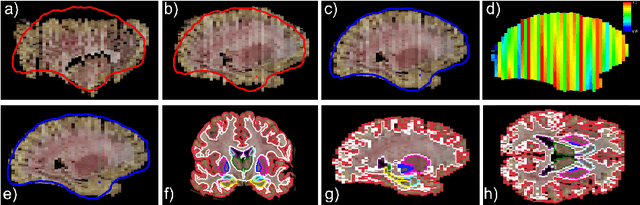

Abstract:Neuroimaging to neuropathology correlation (NTNC) promises to enable the transfer of microscopic signatures of pathology to in vivo imaging with MRI, ultimately enhancing clinical care. NTNC traditionally requires a volumetric MRI scan, acquired either ex vivo or a short time prior to death. Unfortunately, ex vivo MRI is difficult and costly, and recent premortem scans of sufficient quality are seldom available. To bridge this gap, we present methodology to 3D reconstruct and segment full brain image volumes from brain dissection photographs, which are routinely acquired at many brain banks and neuropathology departments. The 3D reconstruction is achieved via a joint registration framework, which uses a reference volume other than MRI. This volume may represent either the sample at hand (e.g., a surface 3D scan) or the general population (a probabilistic atlas). In addition, we present a Bayesian method to segment the 3D reconstructed photographic volumes into 36 neuroanatomical structures, which is robust to nonuniform brightness within and across photographs. We evaluate our methods on a dataset with 24 brains, using Dice scores and volume correlations. The results show that dissection photography is a valid replacement for ex vivo MRI in many volumetric analyses, opening an avenue for MRI-free NTNC, including retrospective data. The code is available at https://github.com/htregidgo/DissectionPhotoVolumes.